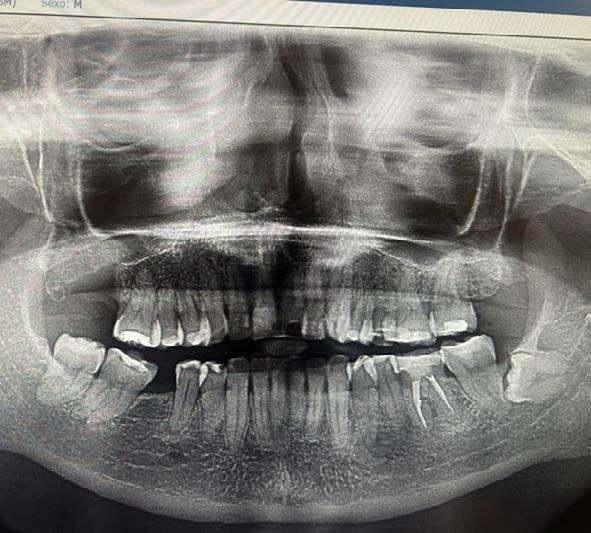

En 2025, la paciente presentó cefalea que posteriormente se localizó en la región maxilar. En consulta externa se realizó la exodoncia del órgano dentario 17 (Figura 2). Debido a la persistencia del dolor y la aparición de una lesión en la tuberosidad maxilar, se llevó a cabo una biopsia, cuyo resultado histopatológico fue compatible con metástasis de carcinoma ductal. Se documentó una lesión sólida de 21 mm que comprometía el hueso maxilar superior derecho, con destrucción ósea e impronta en el seno maxilar. Además, se observó compromiso del espacio graso retromaxilar, así como adoncia del segundo y tercer molar superiores derechos y ganglio submandibular derecho de 11 mm, con características sugestivas de infiltración tumoral (Figura 3).

La evaluación imagenológica mediante tomografía de maxilar y radiografía panorámica mostró una lesión lítica en el lado derecho (Figura 4). Presenta datos de recurrencia de la enfermedad a nivel sistémico en hígado, hueso y pulmón. Ante estos hallazgos, el servicio de mama decidió iniciar tratamiento radioterapéutico dirigido a la región pterigopalatina derecha, administrando una dosis total de 20 g y en 5 fracciones.